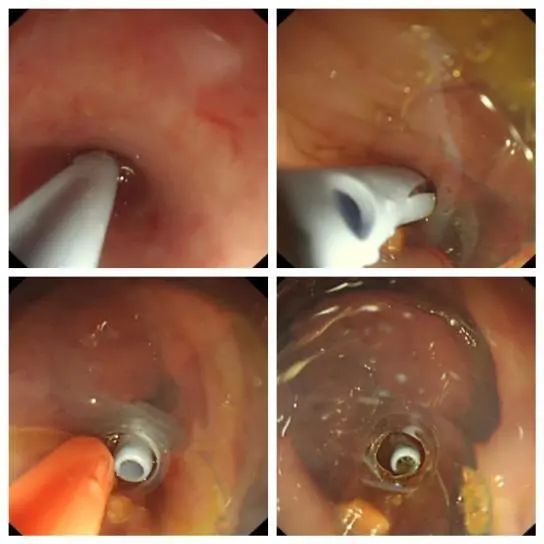

置入斑马导丝,退出子镜,置入阑尾支架。

凯旋而归

X 线确认支架位置合适,退镜结束治疗。术后小朋友自述腹痛明显缓解,术后第一天查房,小朋友腹痛消失,活动自如,感染指标下降;术后第三天复查阑尾支架位置良好,支架通畅,家属对于治疗效果非常满意。